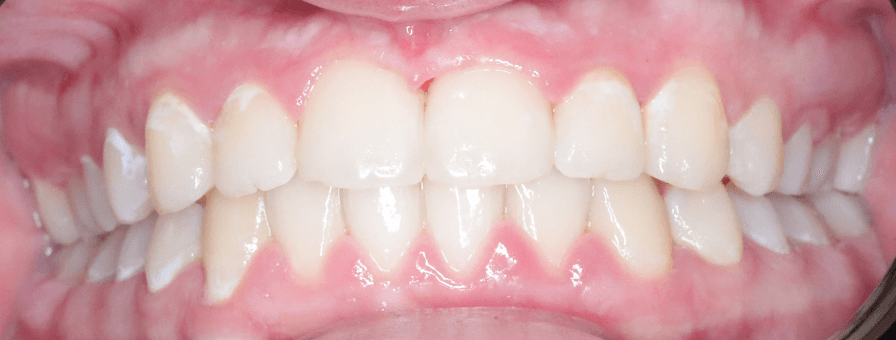

Alinierea Dentară cu Gutiere Spark în 8 Luni

Pentru această pacientă de 27 de ani am recomandat alinierea cu gutiere Spark, o soluție discretă și confortabilă pe care o oferim. Tratamentul s-a finalizat în doar 8 luni.